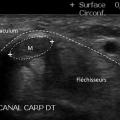

Syndrome du canal carpien

Une autre application de l’échographie en rhumatologie concerne le diagnostic du syndrome du canal carpien. Elle permet de visualiser directement l’épaississement du nerf médian via l’augmentation de sa surface (fig. 3). La surface transversale du nerf médian doit être mesurée au site de son plus grand élargissement, et l’évaluation doit être faite du milieu de l’avant-bras jusqu’à la paume. La présence d’éventuelles anomalies anatomiques causales, comme des kystes ou des hypertrophies des tendons fléchisseurs, peut être recherchée mais est rarement observée.

L’échographie ne remplace pas l’électromyogramme (EMG) et apporte plutôt des renseignements complémentaires. Un consensus d’experts a récemment recommandé d’associer l’échographie à l’EMG car la combinaison de ces deux examens est plus informative que leur utilisation isolée. L’échographie est particulièrement utile dans les cas où les résultats de l’EMG sont atypiques, normaux, ou en cas de récidive après chirurgie.4